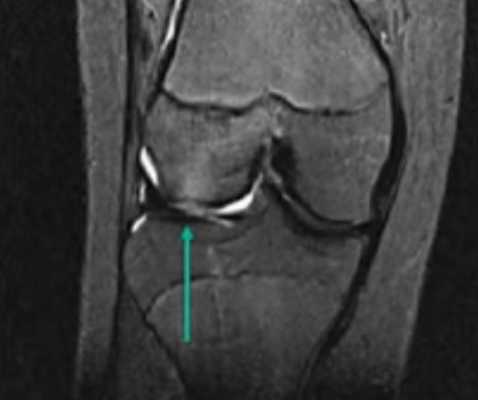

МР-изображение субхондрального перелома латерального мыщелка (зона повреждения указана стрелкой)